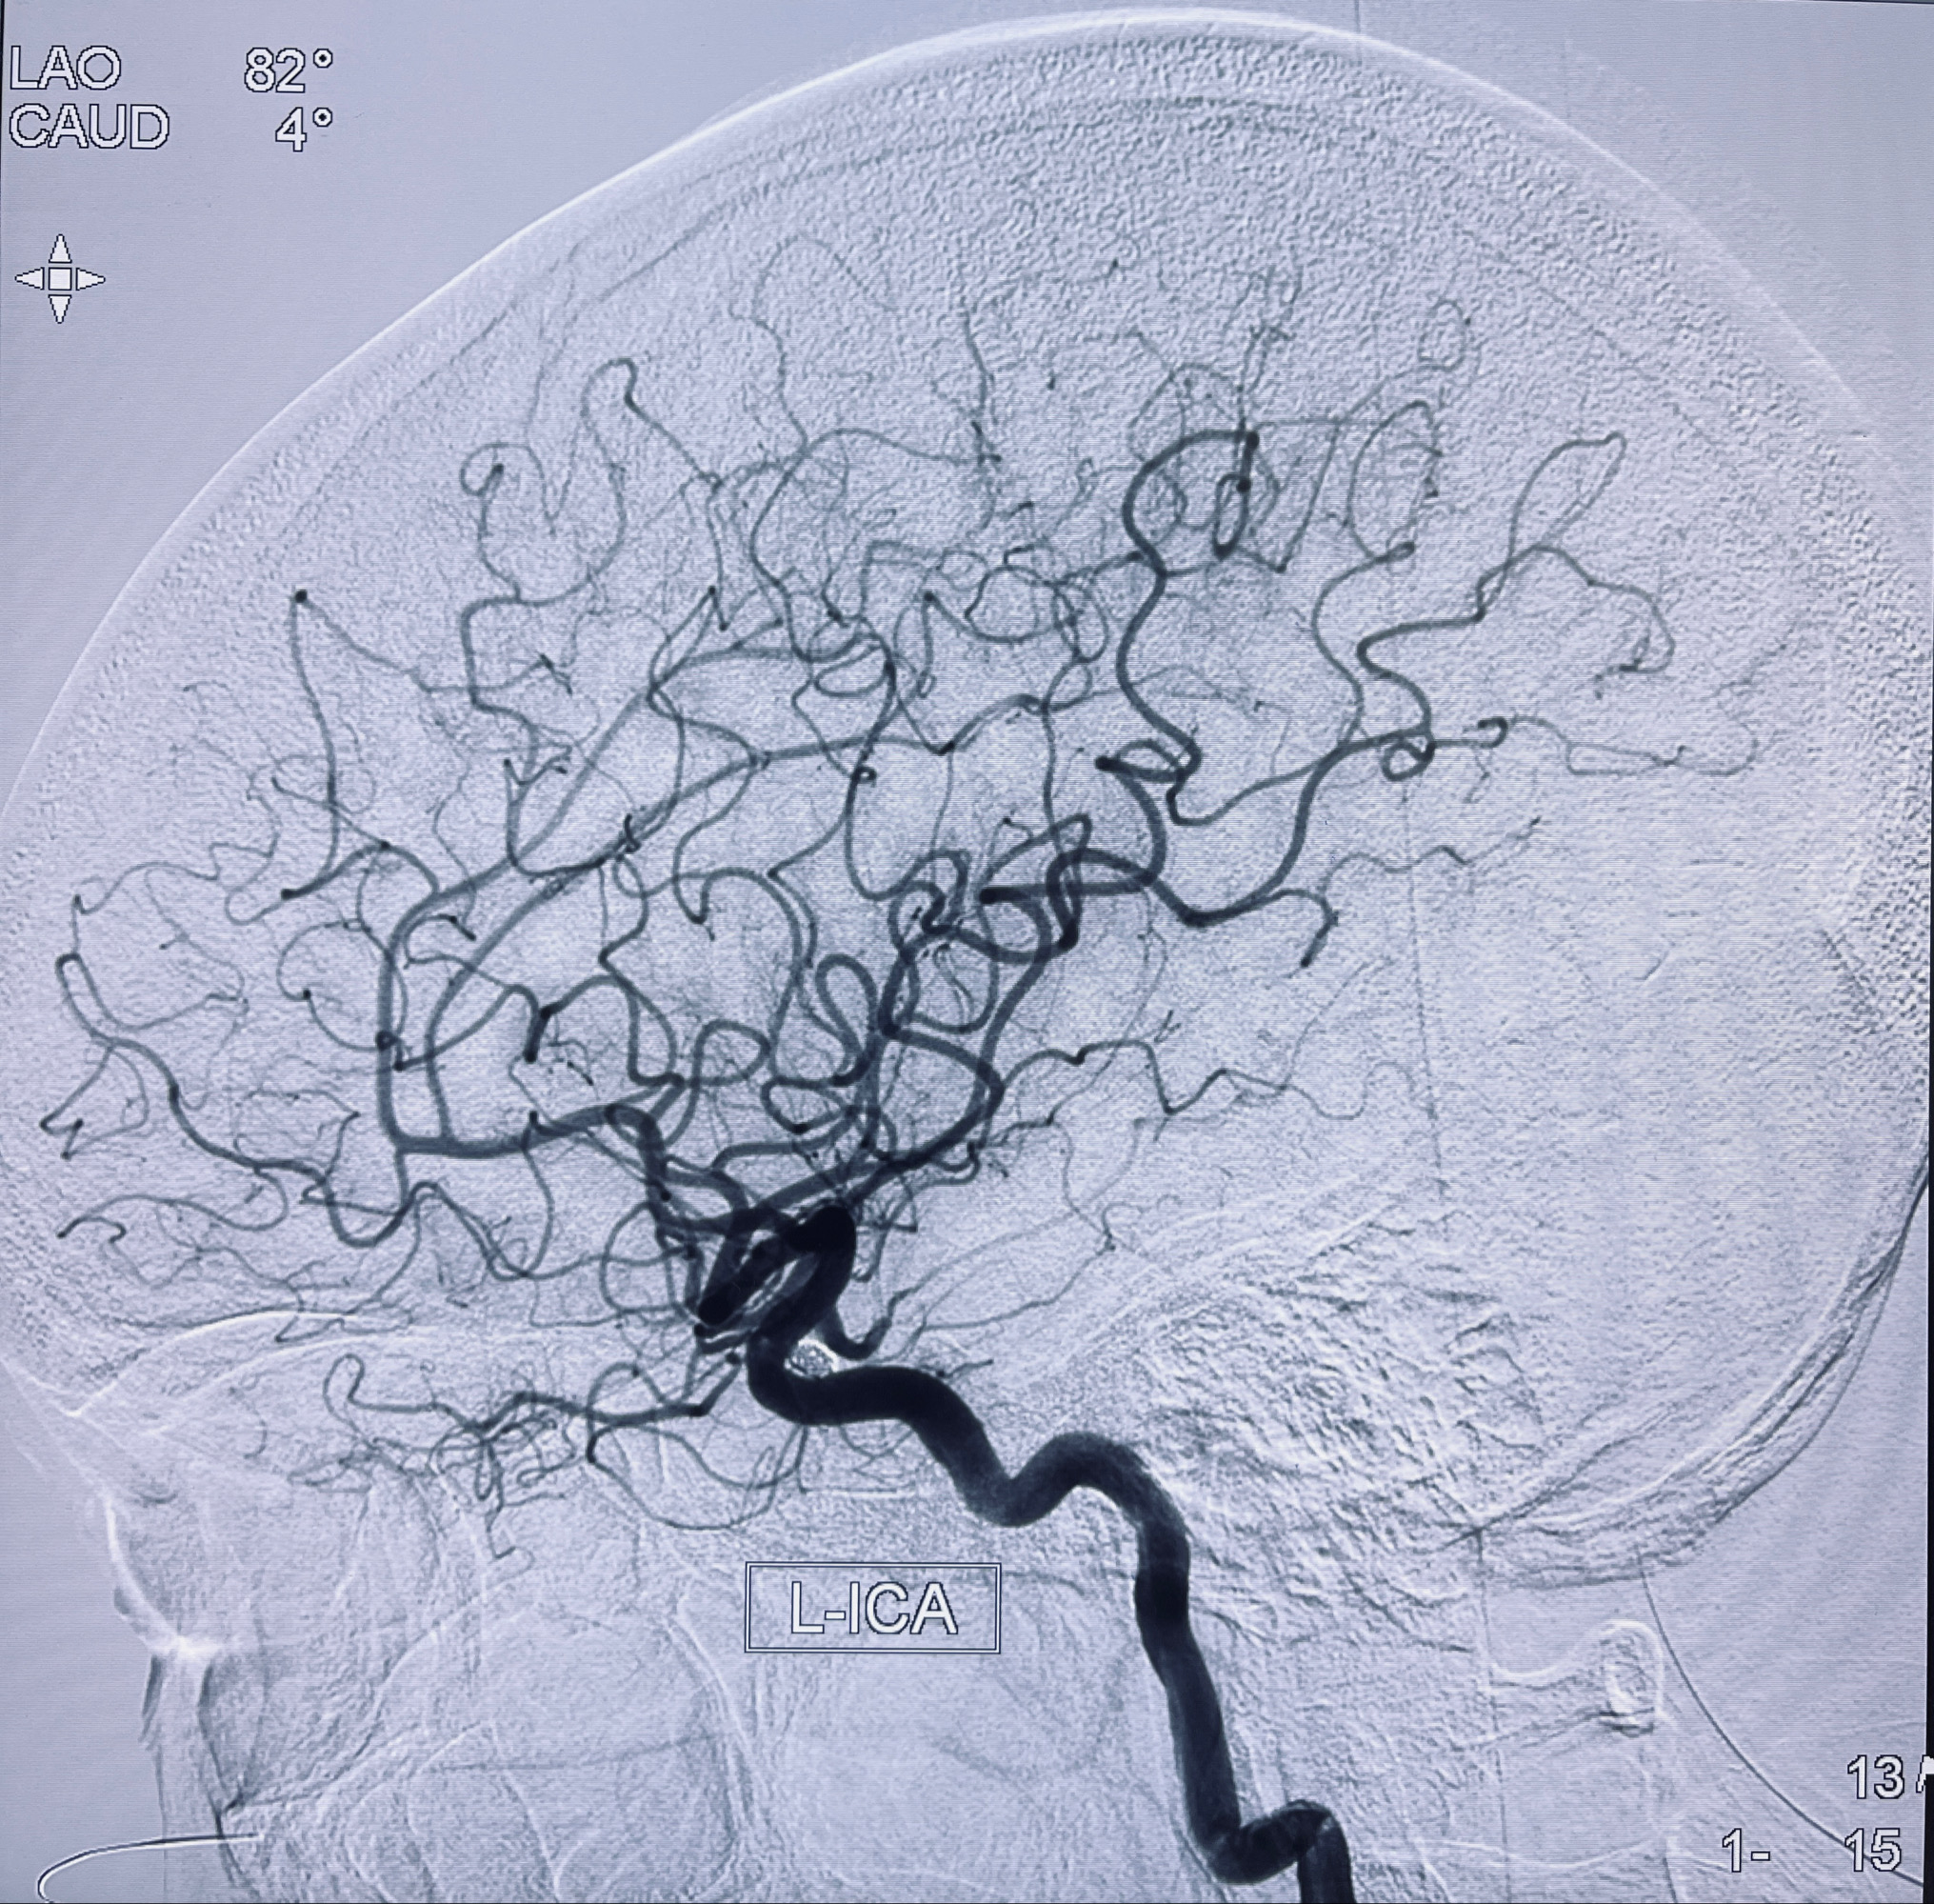

2022-09-29复查DSA